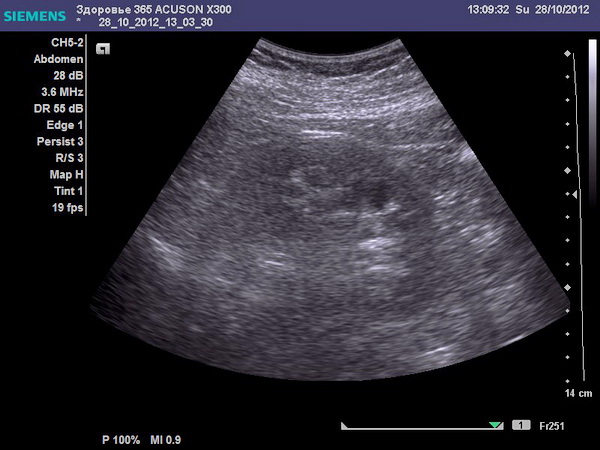

- УЗИ;

Ультразвуковое исследование

Если вы хотите более подробно узнать, что показывает УЗИ позвоночника, а также рассмотреть что показывает, особенности и преимущества, вы можете прочитать статью об этом на нашем портале.

Как правило, этих методов диагностики будет достаточно, чтобы понять, с чем связана боль – непосредственно с почками или же причиной являются проблемы с позвоночной системой. Далее уже больной направляется к узкоспециализированному врачу.

- УЗИ – показывает камни в почках и изменения органов малого таза, ЖКТ.